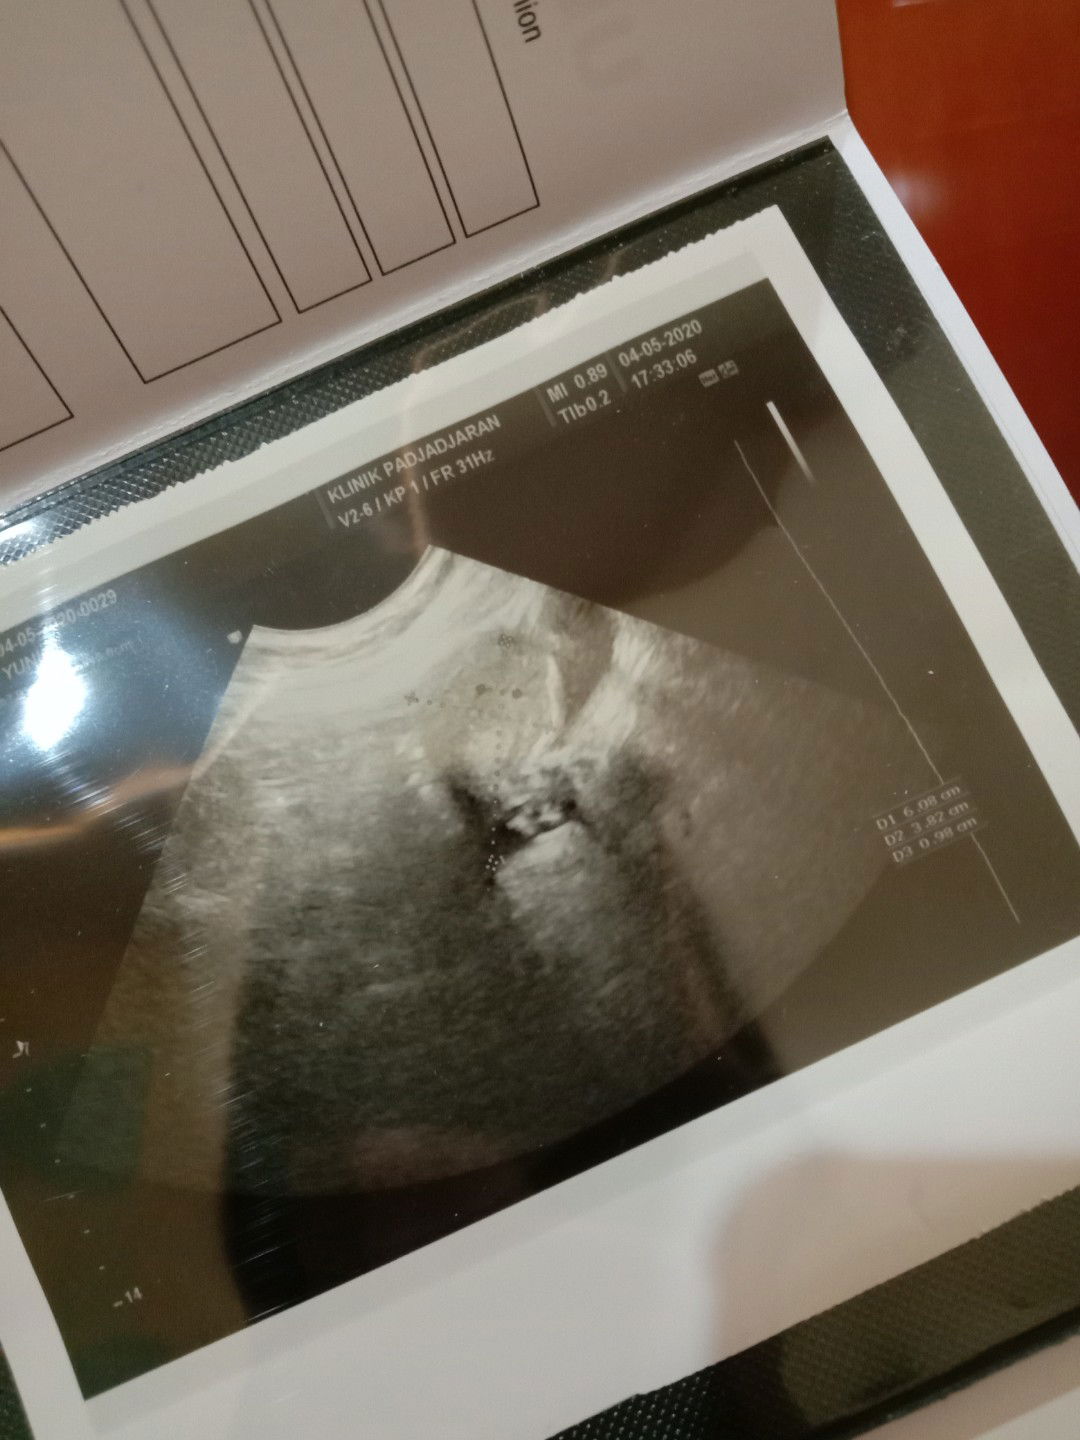

siang bun mau nnya dong ada ga ya yg pengalaman di kehamilan 23minggu tp keluar flek darah campur kya maaf keputihan bening gtu. ga ngerasain skit atau kram juga. saya udh ke dok di ksh penguat, cmn si flek itu dtg nya ga tiap hari, kdang hari ini ada 2hari bru muncul lagi. ga pernah ada di cd juga cmn kluar klo buang air kcil. kta dok sih dd nya baik2 aja, cmn aneh aja ko msh aja keluar ya hehe makasih bundaaa #bantusharing